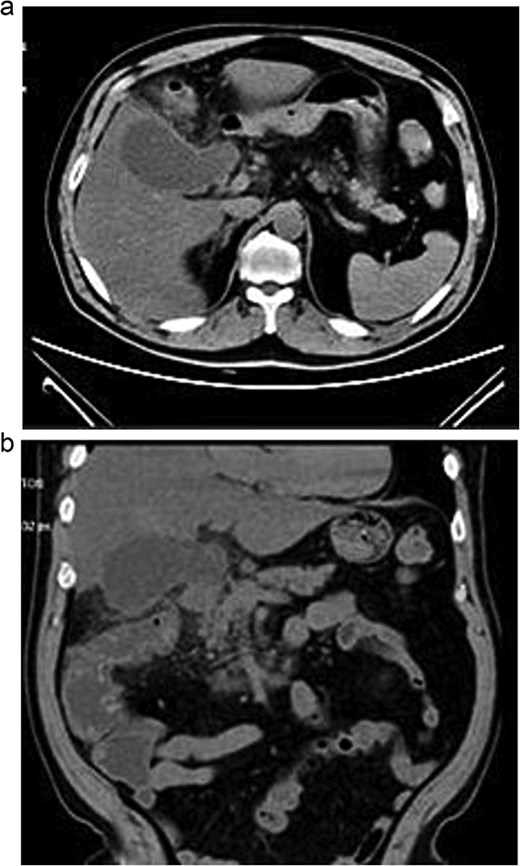

Lab tests showed leukocytosis (15.2 × 103/μl), thrombocytopenia (95.8 × 103/μl), elevated CRP (25.22 mg/dl), procalcitonin (4.49 ng/ml), and total bilirubin (3.5 mg/dl). Liver function was otherwise normal. Ultrasound revealed lithiasic cholecystitis with hydrocholecystosis. Computed tomography (CT) failed to detect duplication (Fig. 1a and b). MRCP confirmed H-type duplicated gallbladder with two independent cystic ducts and mild extrinsic compression of the extrahepatic bile duct (Mirizzi-like pattern) (Figs 2 and 3). MRI sequences (T1 LAVA-Flex and T2 PROPELLER with fat suppression) also demonstrated the duplicated gallbladder and supported the MRCP findings (Fig. 4). No choledocholithiasis was seen.

Axial (a) and coronal (b) abdominal CT showing gallbladder hydrocholecystosis.